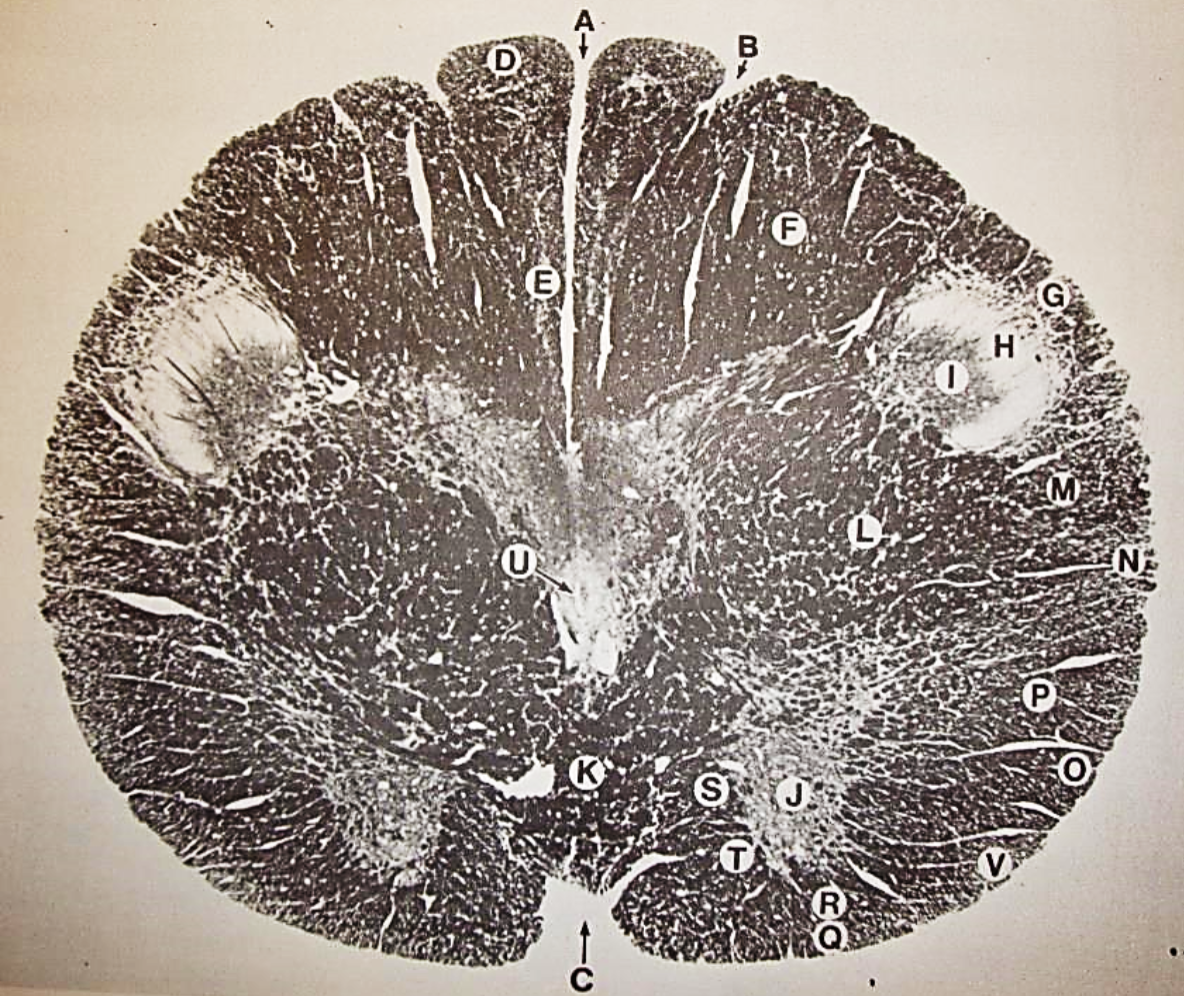

A

Lateral Cuneate nucleus

B

dorsal external arcuate fibers

C + D collectively

vestibular nuclei

C + D collectively

vestibular nuclei

E

dorsal motor nucleus of vagus nerve

F

solitary fasciculus

G

solitary nucleus

H

nucleus ambiguous

I

fascicles of glossopharyngeal nerve

J

hypoglossal nucleus

K

fascicles of hypoglossal nerve

L

dorsal longitudinal fasciculus

M

central tegmental tract

N

inferior olivary nucleus

R

inferior cerebellar peduncle

S

spinal trigeminal tract

T

spinal trigeminal nucleus

U

ventral trigeminothalamic tract

V

pyramidal (corticospinal) tract

W

rubrospinal tract

X

anterior spinocerebellar tract

Y

spinal lemniscus

Z

medial longitudinal fasciculus

a

tectospinal tract

b

medial lemniscus

c

vagus nerve

d

inferior salivatory nucleus